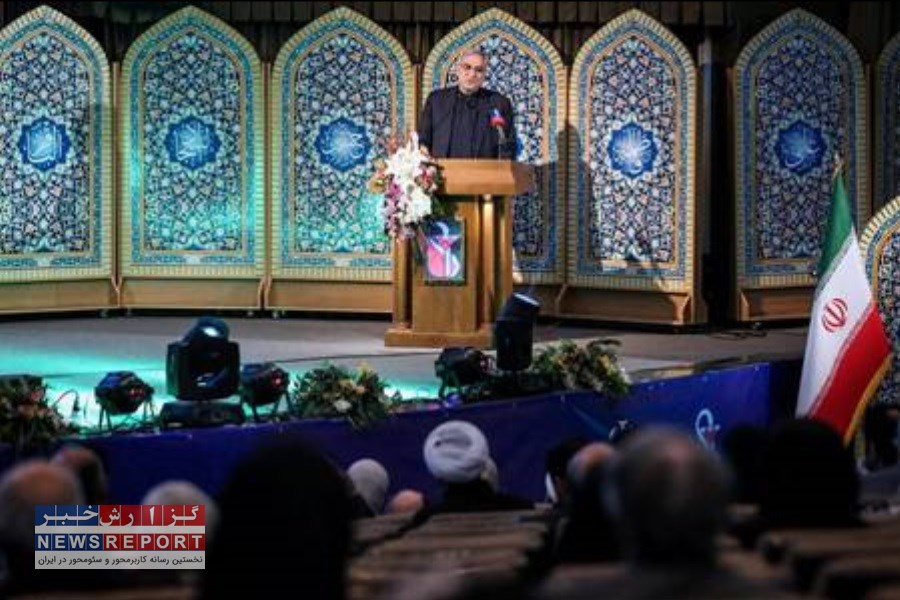

همچنین در این رویداد، خط تولید 5 ماده موثره دارویی ضدسرطان با حضور معاون علمی، فناوری و اقتصاد دانش بنیان رییس جمهور، وزیر صنعت، معدن و تجارت و رییس سازمان غذا و دارو، رونمایی شد.

ولگات اگزما، ولگات D3، ولگات مولتی کیدز، بایوبیون و روژویت، 5 ماده موثره بومی ساخت شرکت زیست تخمیر و مستقر در پارک فناوری پردیس است که این محصولات امروز رونمایی شد.